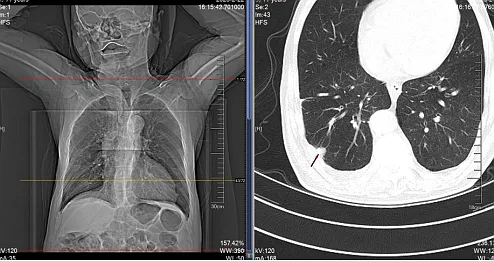

自述胸背痛已有2个月,来诊前近7小时症状加重并伴有双下肢麻木无力。经检查发现,患者胸背部有明显叩痛,双下肢肌力为0级,腱反射消失,大小便不能自主控制。胸椎MRI和CT检查提示胸9-10椎体及附件异常信号影(图1),椎管内脊髓受压严重,同时双肺CT发现右肺占位(图2),考虑为脊柱转移瘤。